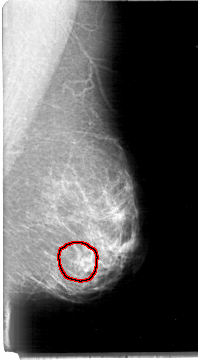

D_4004_1.RIGHT_CC

LEFT_MLO LINES 5386 PIXELS_PER_LINE 2956 BITS_PER_PIXEL 12 RESOLUTION 43.5 OVERLAY

FILE: D_4004_1.LEFT_MLO.OVERLAY

TOTAL_ABNORMALITIES 1

ABNORMALITY 1

LESION_TYPE MASS SHAPE OVAL MARGINS OBSCURED

ASSESSMENT 0

SUBTLETY 3

PATHOLOGY BENIGN

TOTAL_OUTLINES 1

BOUNDARY